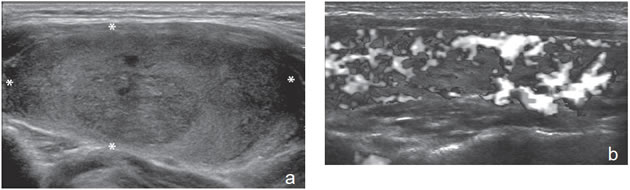

Un nódulo que tiene un componente quístico significativo, usualmente es un nódulo benigno hiperplástico, que ha acumulado abundante coloide (Figura 2a) o bien, un nódulo sólido que ha experimentado un proceso de degeneración colicuativa o hemorragia (Figura 2b). El coloide o el contenido líquido de un nódulo se ve anecogénico (negro en la imagen ecográfica) y las estructuras sólidas se ven ecogénicas (distintos tonos de grises), siendo la ecogenicidad similar al del parénquima tiroideo. En un nódulo sólido la ecoestructura y la ecogenicidad pueden ser variables. En general, la frecuencia de carcinoma es muy baja en nódulos quísticos13 y la mayoría de los carcinomas se presentan como nódulos sólidos (Figura 2c).

Figura 2. a) Quiste coloideo anecogénico y focos ecogénicos (flecha) con artefacto en cola de cometa; b) Nódulo mixto sólido-quístico (cabezas de flechas). Imagen vegetante (flecha) adherida a un tabique que se proyecta al lumen; c) Comparación entre el aspecto ecográfico de un cáncer papilar sólido (flecha abierta) y un quiste coloideo anecogénico.